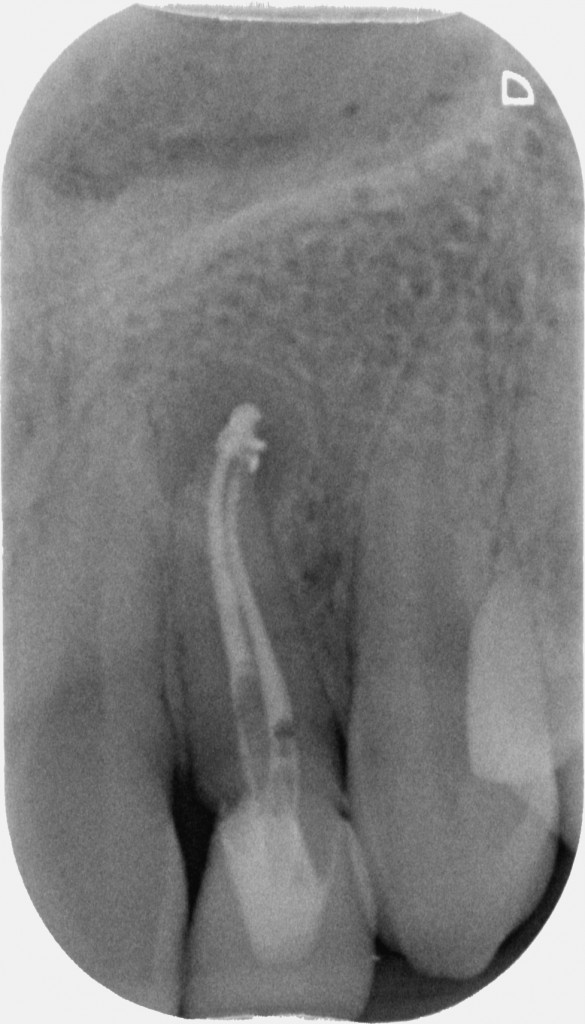

Il primo era questo

La proprietaria del dente, una ragazzina di 16 anni, da tempo lamentava gonfiore e dolore che scompariva solo con terapie antibiotiche. Il dentista precedente aveva semplicemente corretto la forma del dente con un composito orrendo. La diagnosi non aveva saputo farla. Aveva solo saputo dire che era un dente che si poteva solo estrarre.

Con l’ausilio della Cone Beam sono riuscito a identificare che il dente aveva due canali e una radice molto palatoversa: per accedere a questi canali, separati tra loro dall’istmo di smalto invaginato, potevo fare una cavità perpendicolare al dente a livello vestibolare e una palatina.

Non ho smontato subito il composito perché mi serviva a riconoscere i reperi che mi ero cercato sulla tac.

La prima cavità, fuori dagli schemi, ho preferito farla senza diga per capire meglio l’inclinazione. Guarda che spettacolo la cavità di accesso!

Una volta trovato il canale con l’accesso più difficile e sapendo che un secondo canale decorreva parallelo a questo dal lato palatino il resto è stato relativamente semplice.